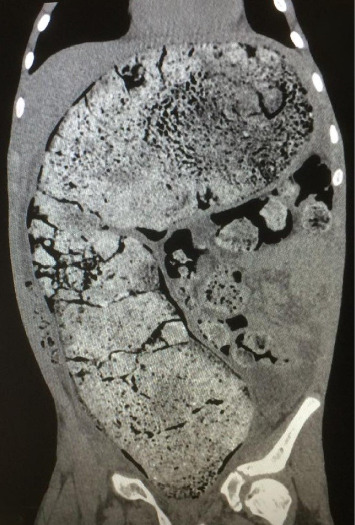

Abdominal compartment syndrome (ACS) in children is a life-threatening complication with high morbidity and mortality. Stressful life events are among the risk factors of functional constipation (FC) in children. We present a 13-year-old male patient with chronic FC due to parents' separation who presented with a history of FC since infancy and inability to defecate during the last month. On examination, the abdomen was distended and tender. His vital signs revealed elevated blood pressure ≥ 95th percentile according to his age weight and gender. On admission, the patient experienced tonic-clonic seizures refractory to medical therapy. He was intubated and a computed tomography (CT) scan revealed an extensive rectosigmoid bowel dilatation. Despite maximal medical support, his condition worsened. ACS was suspected and confirmed via intravesical measurement of intra-abdominal pressure (IAP). An urgent decompression laparotomy (DL) was performed with resection of the affected bowel. His condition improved postoperatively. This case highlights the extremely rare association between ACS and chronic FC resulting from stressful life events.